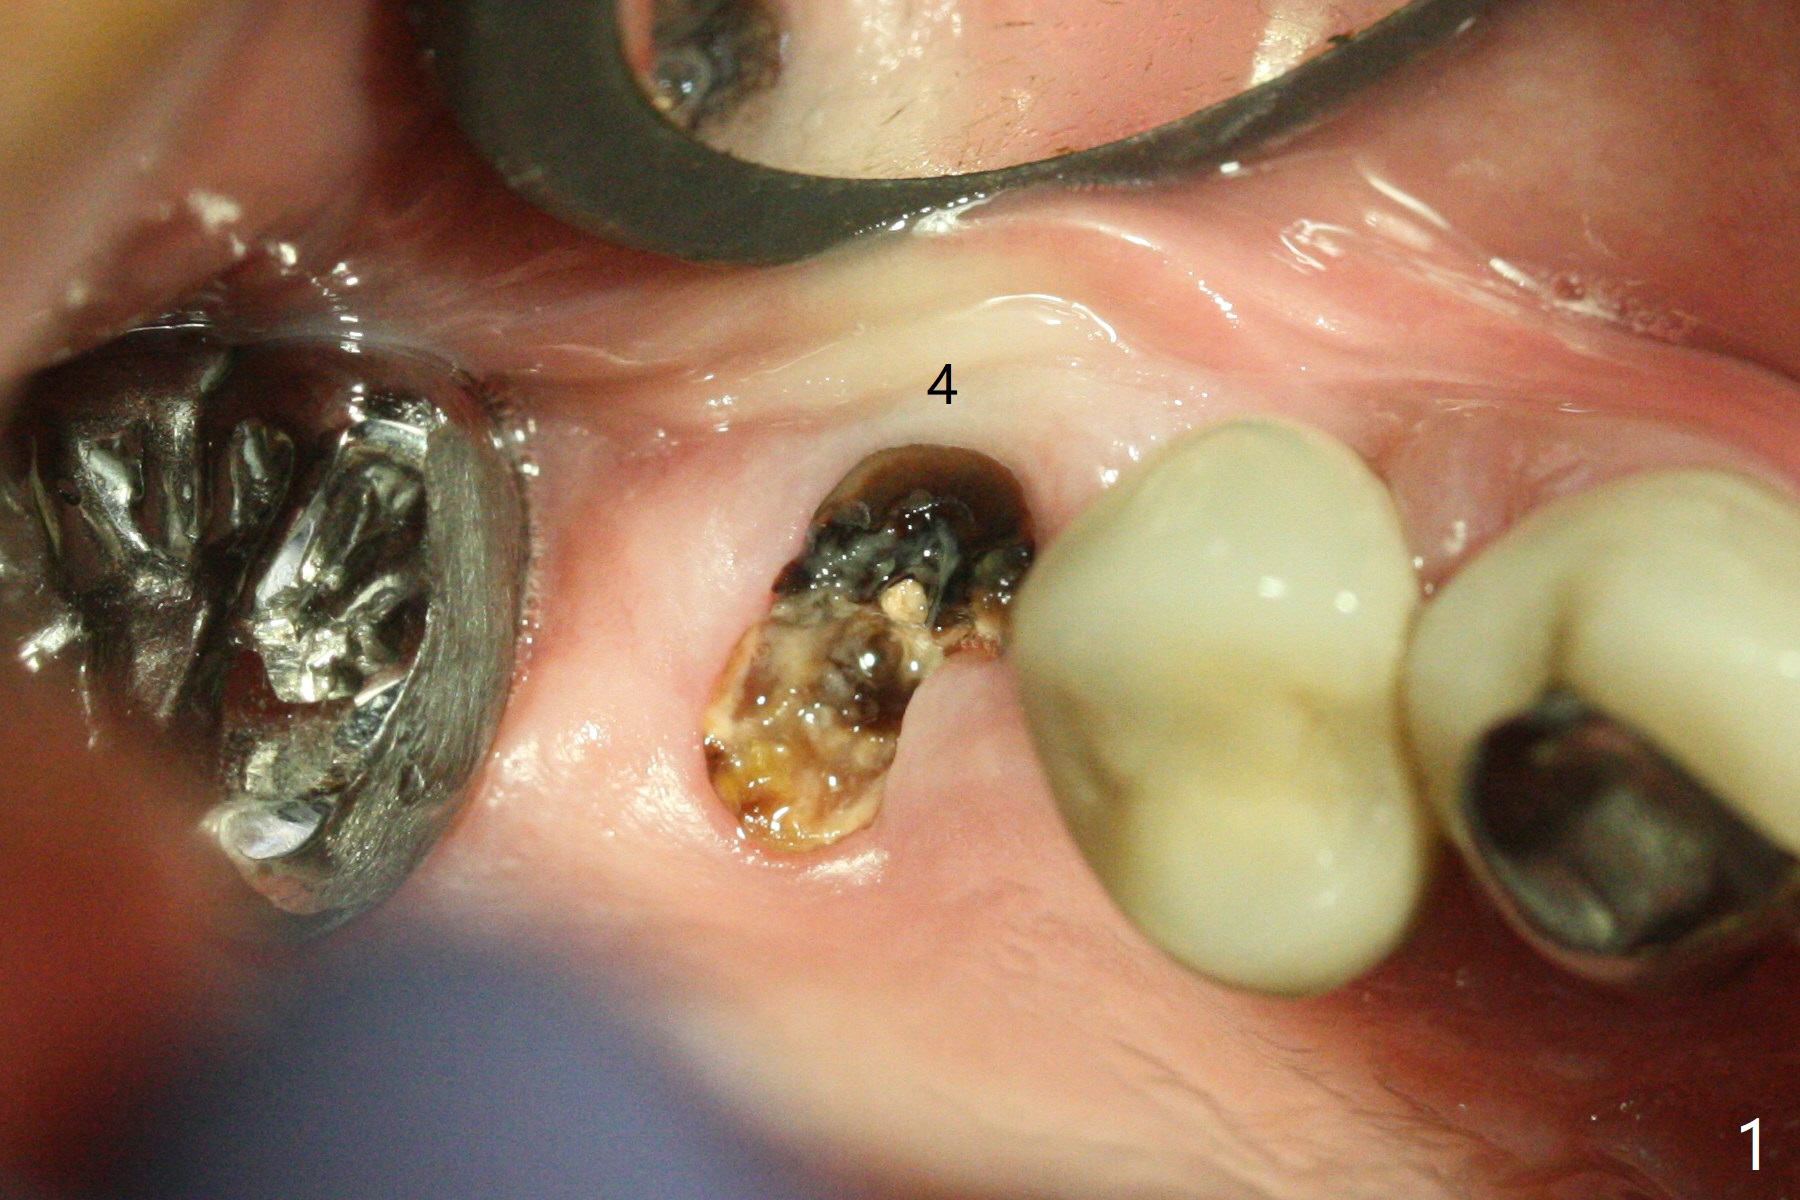

After flattening the root stump with surgical burs and bone trimmer at #4 (Fig.1), it is difficult to use point drill and 2.2x7.3 mm drill because of incomplete engagement of drill cylinder with guide sleeve (Fig.2). The initial osteotomy seems to be buccal. With removal of the remaining root, it is much easier to finish osteotomy (better engagement of drill cylinder with the sleeve) and sinus lift with dummy implants (Fig.3,4 (*: bone graft)). Finally a 4.5x10 mm implant is placed (basically in the middle of the socket with even buccal and palatal gaps) with primary stability and a cemented abutment is hand tightened (after 5.5 mm profile drill) for an immediate provisional (Fig.5). The gingiva is healthy around the provisional with almost perfect seal 2 weeks postop (Fig.6 P). There is no obvious bone loss 7 months postop (Fig.7). There is apparent mature bone in the sinus 9 months postop (Fig.8 *).